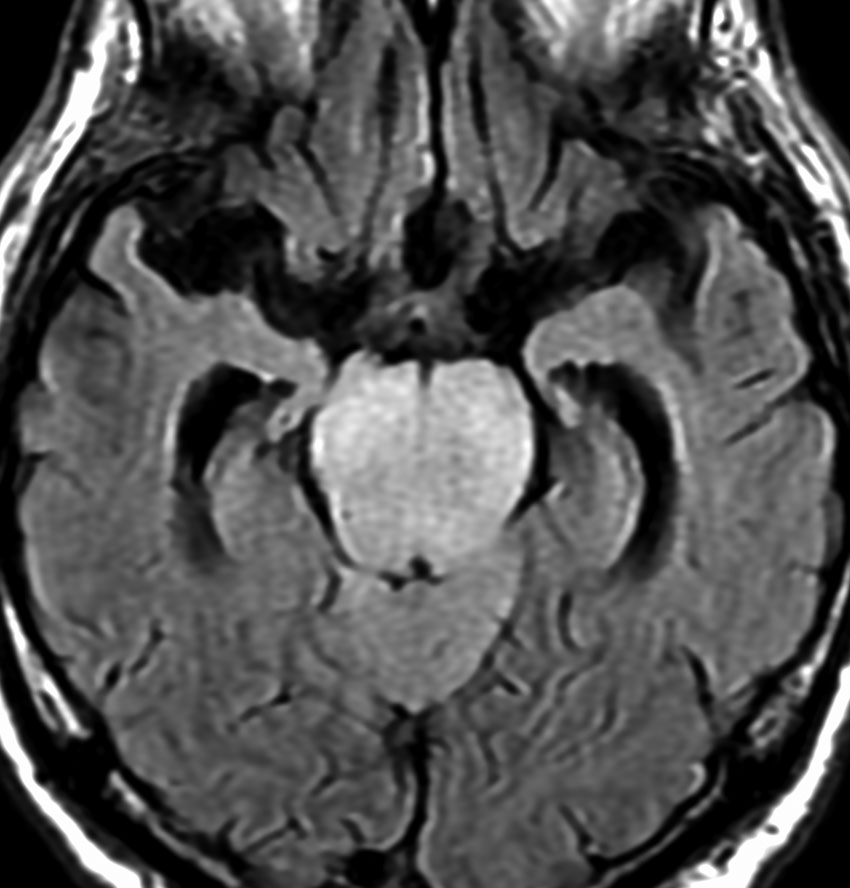

MRI画像所見 60代で嚥下障害と構音障害で発症した例

両側視床から大脳基底核,両側大脳半球深部白質,脳梁まで広範囲に腫瘍が存在します。退形成性星細胞腫のようにまだらにガドリニウム増強されます。